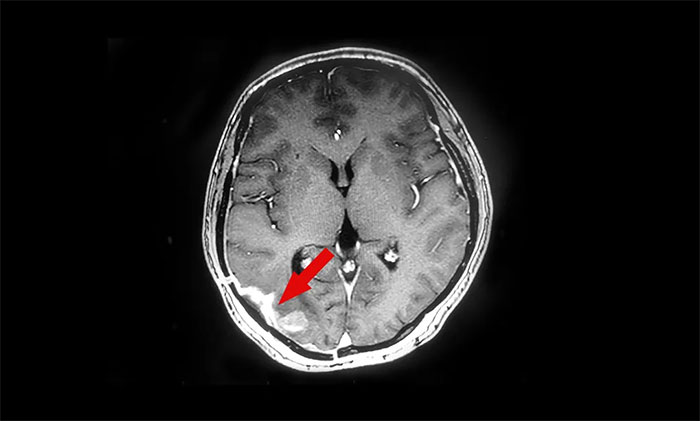

▲治疗前

半年后复查,头颅MR提示颅内肿瘤原位复发,病灶大小约1.5cm*2.3cm,遂至上海蓝十字脑科医院寻求进一步治疗。陈琦主任团队为患者完善相关检查,并开展MDT多学科会诊评估,符合伽玛刀治疗适应症。治疗期间,患者健康状况平稳,未出现明显并发症。